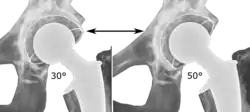

The direction of the acetabular cup influences the range of motion of the leg, and also affects the risk of dislocation.[16] For this purpose, the acetabular inclination and the acetabular anteversion are measurements of cup angulation in the coronal plane and the sagittal plane, respectively.

![Acetabular inclination.[95] This parameter is calculated on an anteroposterior radiograph as the angle between a line through the lateral and medial margins of the acetabular cup and the transischial line which is tangential to the inferior margins of the ischium bones.[95]](./_assets_/Acetabular_inclination_of_hip_prosthesis.jpg)

![Acetabular inclination is normally between 30 and 50°.[95] A larger angle increases the risk of dislocation.[16]](./_assets_/Range_of_acetabular_inclination.png)